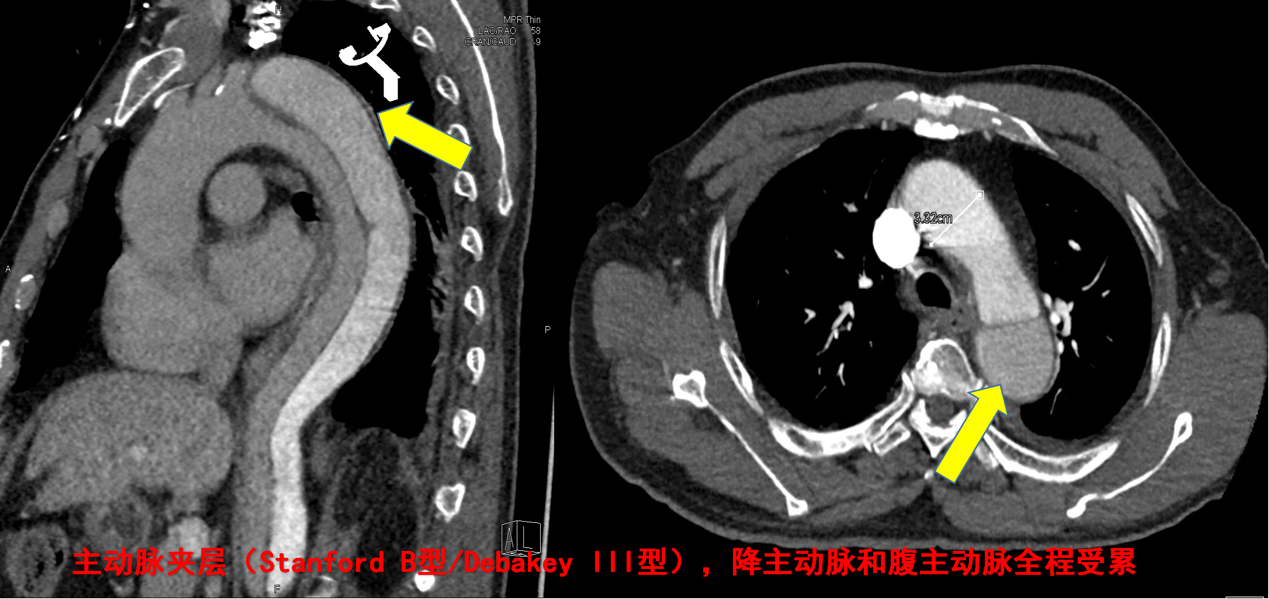

男,65岁,主动脉夹层(Stanford B型/Debakey III型),降主动脉和腹主动脉全程受累(见CTA箭头处),急诊行主动脉覆膜支架植入术,支架植入术后夹层消失,手术十分顺利。

术前造影结果显示: